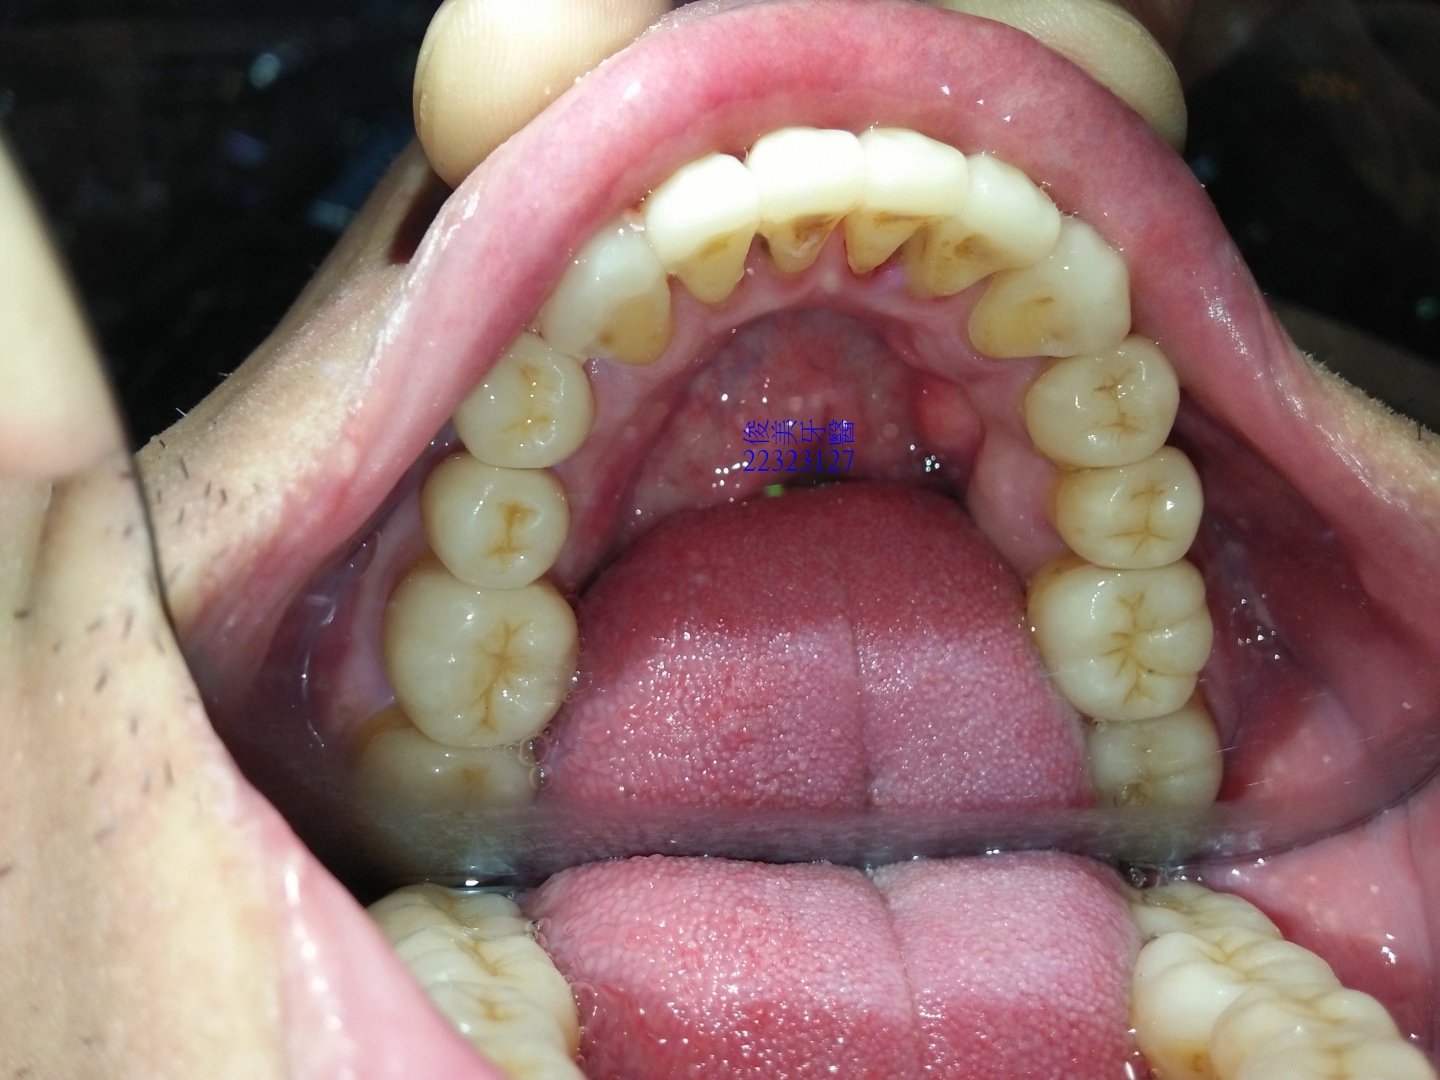

下顎原始狀況。牙齒開始內傾到舌側位置。

後牙咬合高度逐漸變低。

後牙咬合高度逐漸變低;犬齒受力大,高度剩下2/3,切端皆已磨損喪失。